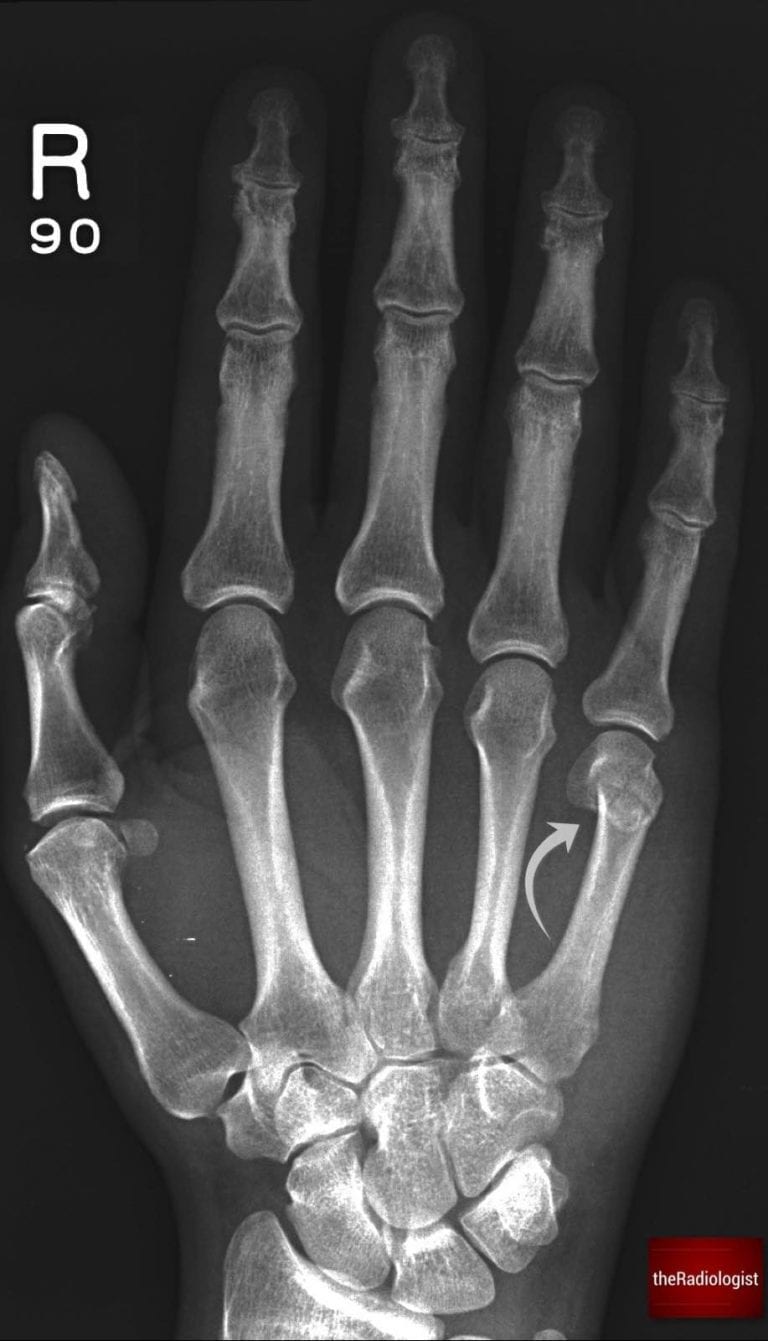

2. Metacarpals

An indented fourth or fifth metacarpal head is a classic sign of a Boxer’s fracture following a punching injury.

Here we have an example of a Boxer’s fracture – look for indentation at the heads of the fourth and fifth metacarpal.

Don’t stop there: trace an imaginary line across the bases of the metacarpals. Normally this will be continuous, but in some cases the fourth or fifth metacarpals can dislocate and drop downwards, overlapping the carpal bones and breaking the line. Overlapping bones on a hand X-ray should always make you think about dislocation.

Trace a line across the base of the metacarpals – this should be continuous. If a metacarpal base drops downwards it could be dislocated.

KEY POINT

Don’t forget to trace a line across the base of the metacarpals. A metacarpal dislocation can be subtle and easily missed.